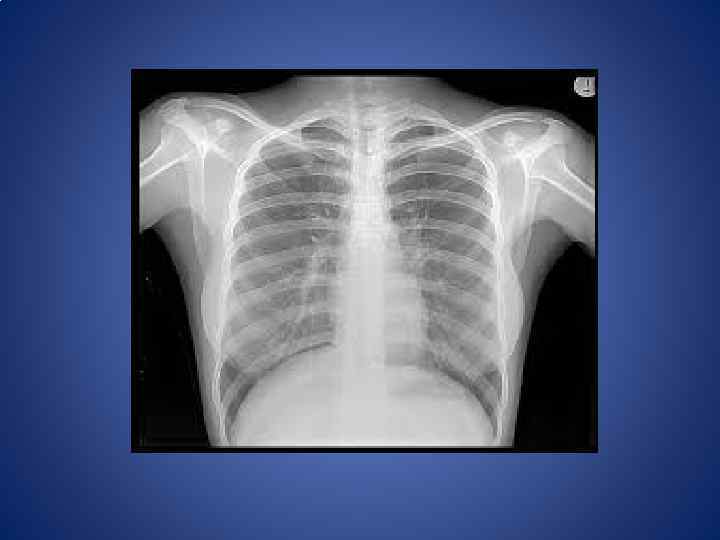

Diagnosis The most important screening tool remains the medical history: the character of the complaints and any specific symptoms (fatigue, weight loss, unexplained anemia, fever of unknown origin, paraneoplastic phenomena and other signs). Sometimes a physical examination will reveal the location of a malignancy. Diagnostic methods include: Biopsy, either incisional or excisional, or Resection; are the only ways that a definitive diagnosis of cancer can be made. Endoscopy, either upper or lower gastrointestinal, bronchoscopy, or nasendoscopy; X-rays, CT scanning, MRI scanning, PET scan, ultrasound and other radiological techniques; Scintigraphy, Single Photon Emission Computed Tomography, Positron emission tomography and other methods of nuclear medicine; Blood tests, including tumor markers, which can increase the suspicion of certain types of tumors or even be pathognomonic of a particular disease.